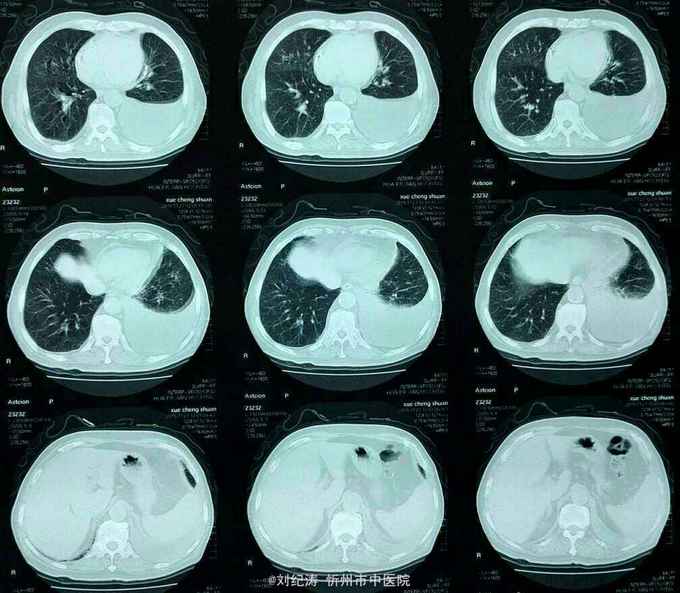

查体:ECOG评分:3分,生命指征平稳,浅表淋巴结未触及明显肿大,双眼睑无水肿,唇无发绀,颈软,双侧胸廓对称,左肺语颤增强,左肺呼吸音消失,右肺呼吸音粗,可闻及哮鸣音,心律齐,腹平软,肝脾肋下未触及,移动性浊音阴性,肠鸣音3次/分,双下肢无水肿。 辅助检查:血常规(2016.1.1):WBC:10.6*109/L,RBC:4.69*1012/L, PLT:165*109/L ,HGB:167g/L.生化(2016.1.1):谷丙转氨酶11U/L,谷草转氨酶11U/L,总蛋白60g/L,白蛋白33g/L,尿素:9.8mmol/L,肌酐:123umol/L,尿酸:251 umol/L,血糖:7.37 mmol/L;电解质:钾:4.79mmol/L,钠:123.5 mmol/L,氯:85.7 mmol/L,钙:2.03 mmol/L。肺部CT(2016.1.1):左肺完全萎缩,左侧胸腔大量积液,右肺未见异常,纵膈轻度右移,未见明显肿大淋巴结。

诊断: 1.左肺癌 左侧胸腔积液 左肺不张;2.2型糖尿病;3.低钠、低氯血症;4.低蛋白血症 治疗 完善检查,予以胸腔穿刺置管引流胸水以减轻心肺负荷,静脉给予抗感染、祛痰、止咳、平喘、提高免疫、扶正抑瘤、营养支持、调节电解质平衡及对症治疗。